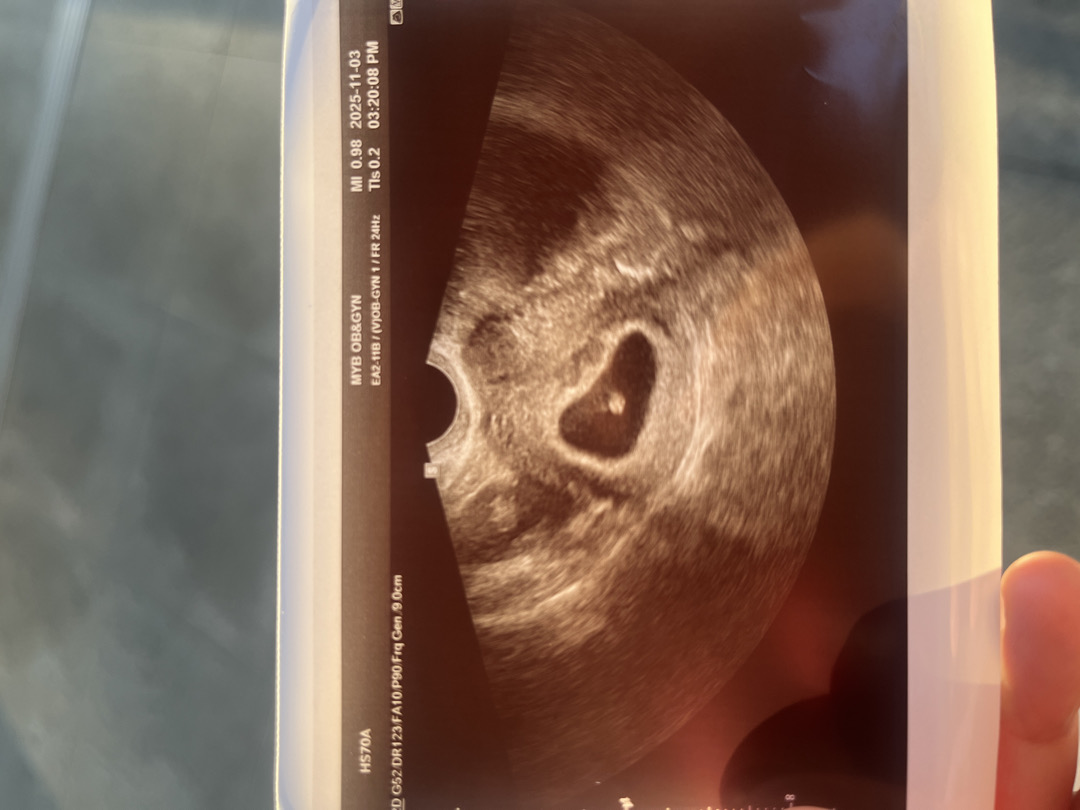

저는 6주5일로 추정되고 8mm에 140뛰는거 확인하고 왔어용😍

(6주4일)ㅎㅎ오늘 드디어 아기를 보고왔어오!

세번째 진료보고왔습니다! 첫진료는 일반산부인과에서 아기집크기보고 5주1일이라고 해주셔서 그렇게알고있었는데 지난주 출산병원에서 명확한 난황보았고! 오늘 기존대로라면 7주1일인데 이제 아기모양이 생겨서 아기사이즈로 6주4일 판정받았습니다~ 심장소리들었는데 너무신기해요! 사실 아직 그렇다할 임신증상이없어서 두려웠거든여ㅠㅠ 저는 7.6mm이에요 다른분들은 어떠신가요?ㅎㅎ 다음진료는 3주뒤라는데 이벤트없이 잘 지나가길 바래봅니다🥰